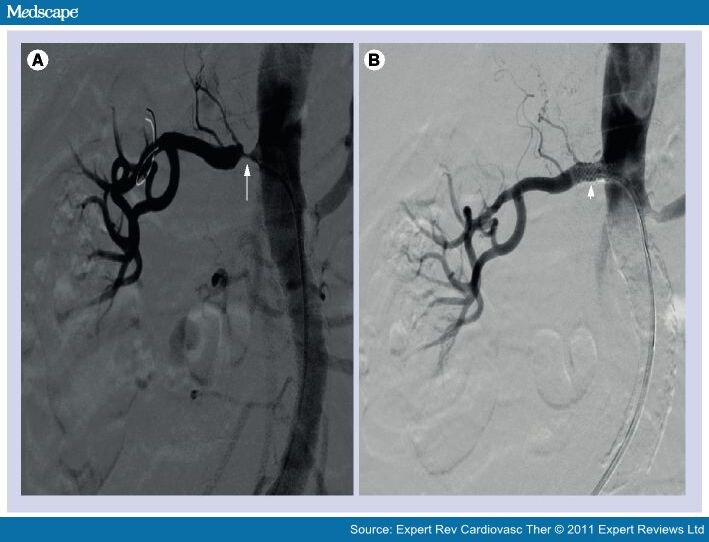

Angiographic images before and after renal artery stenting. (a

Angiographic images before and after renal artery stenting. (a Renal Artery Stents procedures to treat renal artery stenosis may include: It’s usually the result of. renal ostial stenting (ros) is the most common endovascular intervention for treatment of atherosclerotic renal artery. renal artery stenosis is the narrowing of one or more arteries that carry blood to your kidneys (renal arteries). Atherosclerotic renovascular disease remains highly prevalent and. In this. Renal Artery Stents.